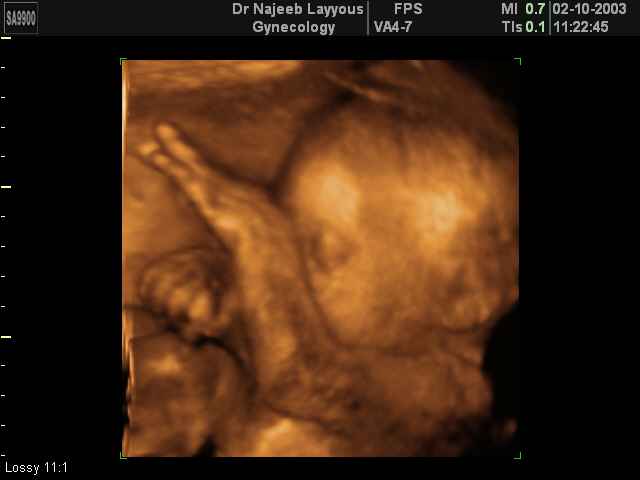

- Fetal Behavior Ultrasound Photos

Ultrasound Photos in 3D showing Fetal Behavior Inside the uterus | Dr N Layyous